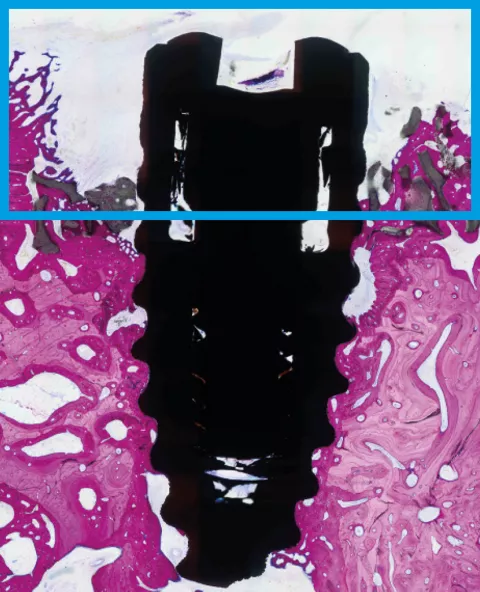

Bone defects can greatly compromise the predictability of osseointegration. In a recent preclinical study22, SLActive® showed significantly higher formation of new bone aggregate within eight weeks compared to the standard Straumann® SLA® hydrophobic surface.

Bone aggregate formation at 8 weeks.22

22 El Chaar E, Zhang L, Zhou Y, et al. Osseointegration of Superhydrophilic Implants Placed in Defect Grafted Bones. International Journal of Oral & Maxillofacial Implants . Mar/Apr2019, Vol. 34 Issue 2, p443-450